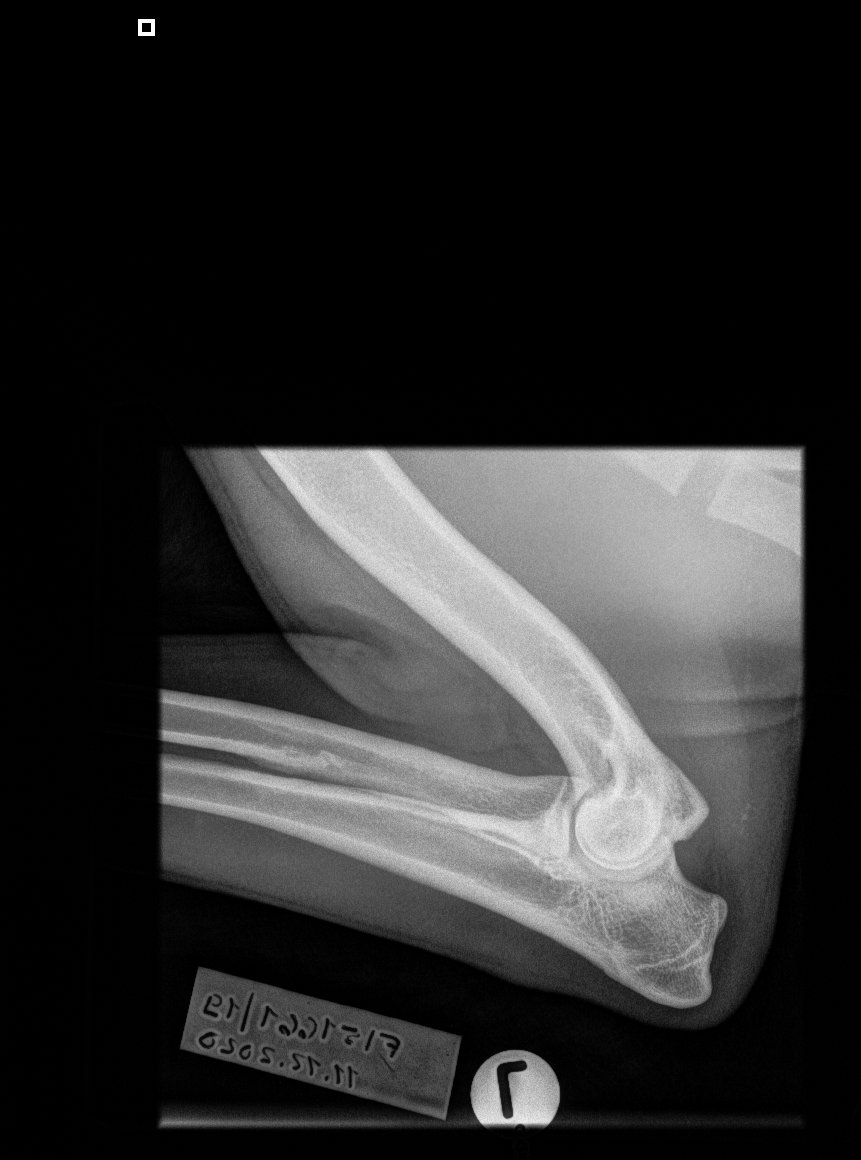

» HD A/A » ED 0/0 » silmät OK » Selkä LTV0 » Polvet 0/0